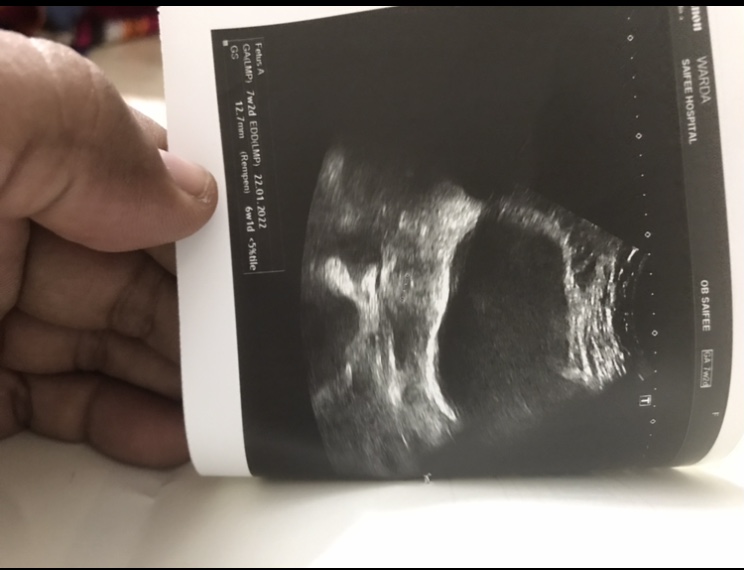

Weight 78 Age 23 LMP 17 Apr

BhCG reports attached ( 4 times test done)

Ultrasound attached.

- In which week my wife is?

- Pls suggest what to do? Is it pregnancy or not?